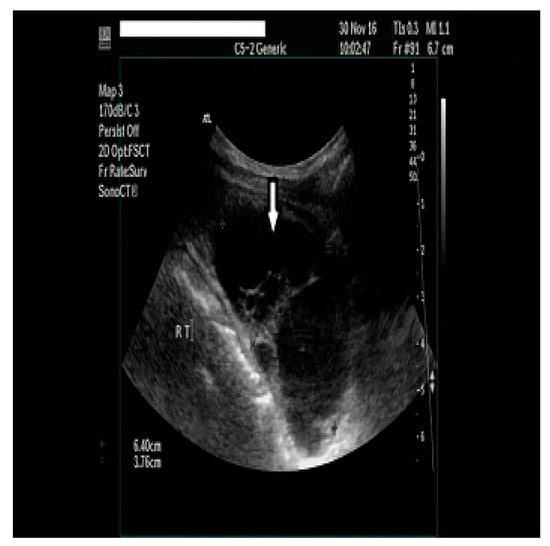

2. Case Presentation

2.1. Diagnostic Assessment